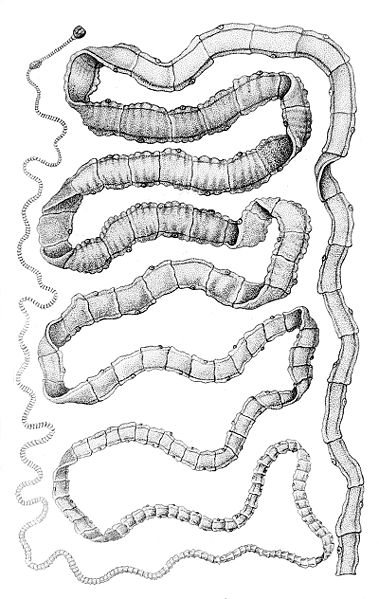

3. Sán dây

Còn được gọi với cái tên Taenia, loài giun hình dải ruy băng này có thể khiến bạn bị co giật nếu nó hình thành các u nang bên trong não của bạn. Tuy nhiên, nơi định cư phổ biến nhất của chúng là ở trong ruột của con người (hoặc vật nuôi).

Ấu trùng Taenia Solium có thể xâm nhập vào bên trong cơ thể một người khi người đó uống nước bị ô nhiễm hoặc ăn thịt lợn, thịt bò chưa nấu chín có chứa nang hoặc trứng sán dây.

Không phải mọi người nhiễm sán dây đều bị co giật, nó chỉ xảy ra khi ấu trùng Taenia ảnh hưởng đến hệ thần kinh trung ương ở người. Trong những trường hợp này, hầu như không thể chẩn đoán hoặc điều trị nhiễm sán dây vì bệnh nhân không có bất kỳ triệu chứng nào. Thông thường, loài này sẽ ảnh hưởng đến ruột non và gây táo bón, tiêu chảy, đau bụng,… Trong trường hợp nặng hơn, có thể dẫn đến động kinh, mù mắt, viêm màng não và nhiều vấn đề thần kinh khác. Sán dây là nguyên nhân của 30% các trường hợp động kinh ở nhiều vùng lưu hành dịch bệnh nơi người và lợn thả rong sống gần nhau.

Sán dây cũng là một trong những loại ký sinh trùng nguy hiểm phổ biến. Người ta ước tính rằng 5% người Mỹ có sán dây, nhưng hầu hết không nhận thức được điều này.